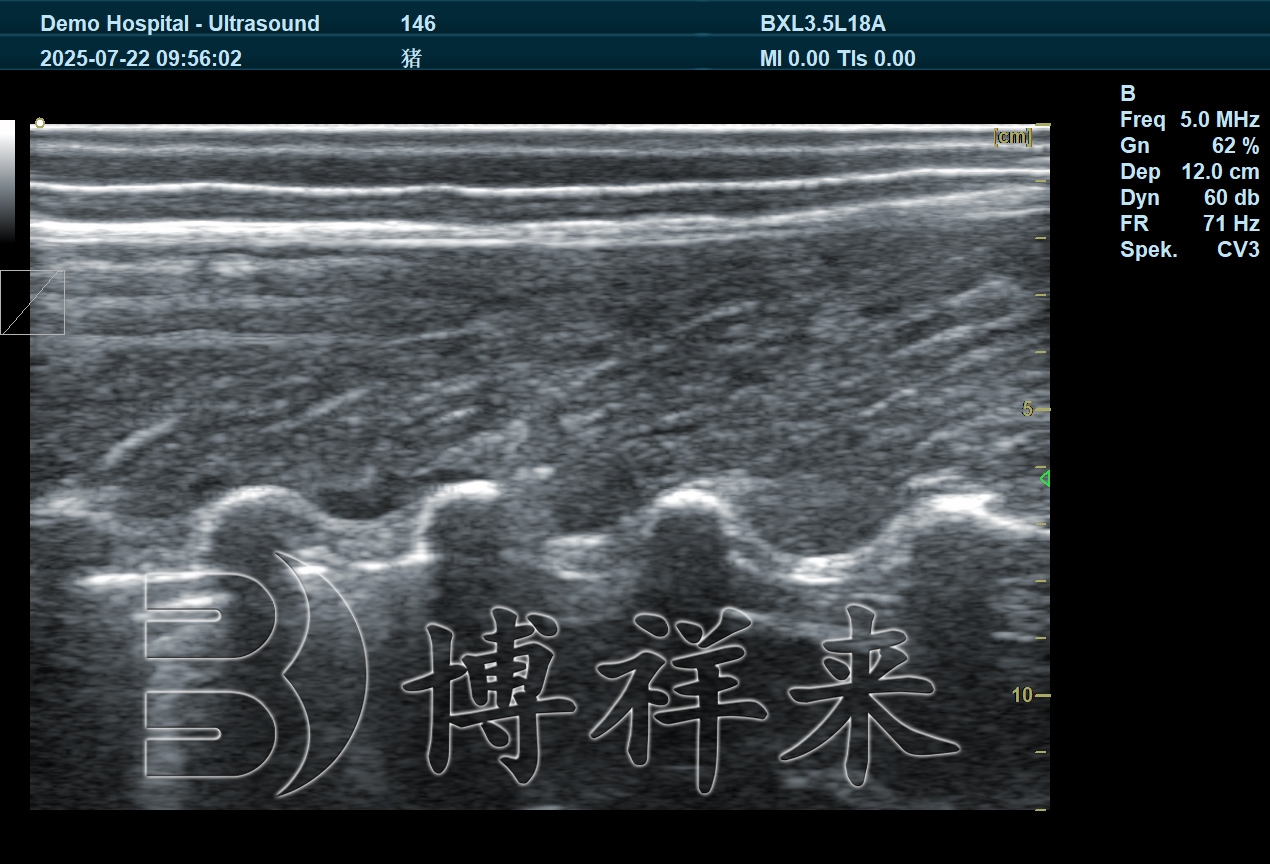

猪背膘仪的技术原理与优势

猪背膘仪通常基于兽用超声成像原理,通过专用探头获取背部脂肪层与肌肉层的回声信息,从而准确测量背膘厚度。相较于人工触摸或目测评估,猪背膘仪能够清晰区分皮肤、脂肪和肌肉结构,使测量结果更加客观、可重复。

在技术应用层面,猪背膘仪具有操作直观、测量速度快、数据稳定性强等特点,特别适合在规模化猪场中进行批量检测,为繁殖管理提供可靠的数据支持。